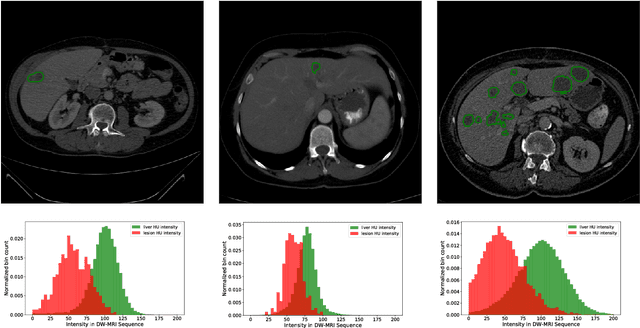

Abstract:The segmentation of liver lesions is crucial for detection, diagnosis and monitoring progression of liver cancer. However, design of accurate automated methods remains challenging due to high noise in CT scans, low contrast between liver and lesions, as well as large lesion variability. We propose a 3D automatic, unsupervised method for liver lesions segmentation using a phase separation approach. It is assumed that liver is a mixture of two phases: healthy liver and lesions, represented by different image intensities polluted by noise. The Cahn-Hilliard equation is used to remove the noise and separate the mixture into two distinct phases with well-defined interfaces. This simplifies the lesion detection and segmentation task drastically and enables to segment liver lesions by thresholding the Cahn-Hilliard solution. The method was tested on 3Dircadb and LITS dataset.